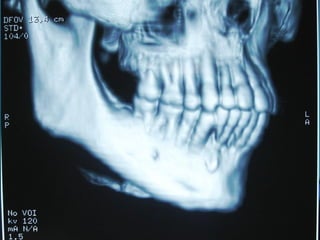

Eliminación de focos sépticos en bloque en paciente con osteitis

mandibular crónica

Osteitis

Imagen microscópica de osteitis, inicialmente existe una etapa de

osteoclastosis seguida por regeneración. No siempre el hueso

regenera en su totalidad y sigue el curso de cualquier inflamación

dejando un area de tejido fibroso que con el tiempo puede

calcificarse (hueso denso)

Manejo con antibióticos obligado

Revisión periódica